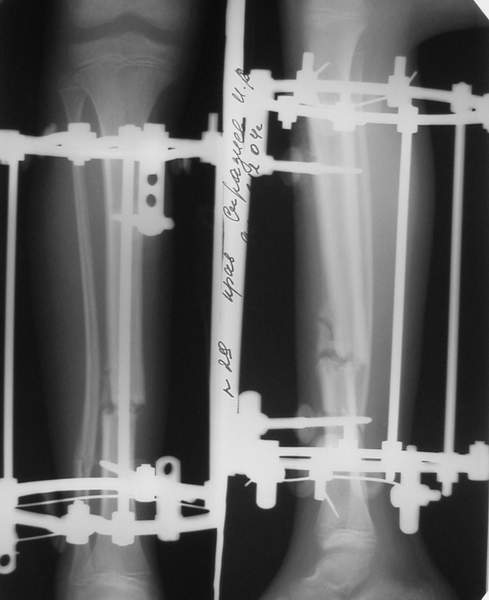

3a

3b

3c

В аттачте № 3 - один из примеров полукольцевого аппарат...

Это уже я баловался.

Итог? Работы больше (по времени и

интраоп "подгонке"), срастается также, а особого преимущества по сравнению с

"чиста" кольцевым (вес, удобство ношения и пр.) - я, по крайней мере,

не нашел.

Теперь не балуюсь.

Может быть зря?

;-)

МТ мы используем, конечно, не только на голени. В прилагаемом примере у парня при поступлении была наружная ротация 40 гр. и "полумертвый" коленный сустав. Можно был бы, конечно, до конца использовать полную компоновку. Но для того он и есть метод выбора.